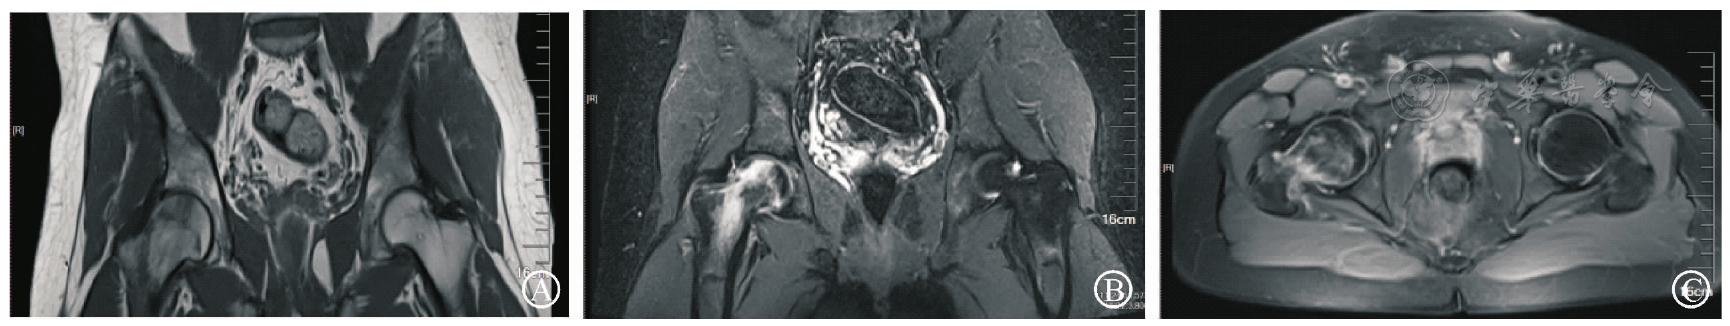

图2 患者2018年5月入院时双髋影像学图像。图A为双髋X线正位片,示双髋正常;图B为双髋MRI冠状面T1WI像,示左侧股骨头颈部骨髓水肿;图C为双髋MRI冠状面STIR像,示左侧股骨头颈部骨髓水肿;图D为双髋MRI横截面STIR像,示左侧股骨头颈部骨髓水肿

图3 患者2018年9月复诊双髋MRI。图A为双髋MRI冠状面T1WI像,示左侧股骨头颈部无骨髓水肿;图B为双髋MRI冠状面STIR像,示左侧股骨头颈部无骨髓水肿;图C为双髋MRI横截面STIR像,示左侧股骨头颈部无骨髓水肿